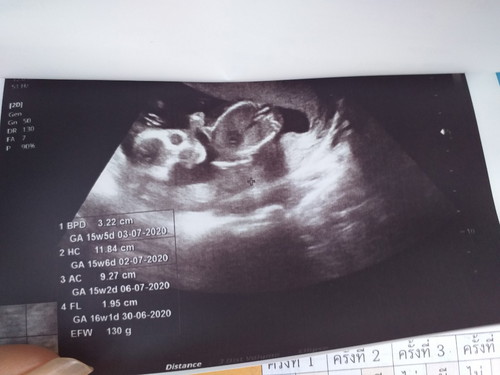

อยากทราบว่าลูกขนาดเท่าไหร่ หนักเท่าไหร่ ดูในใบซาวด์ตรงไหนค่ะ

EFW ค่ะ